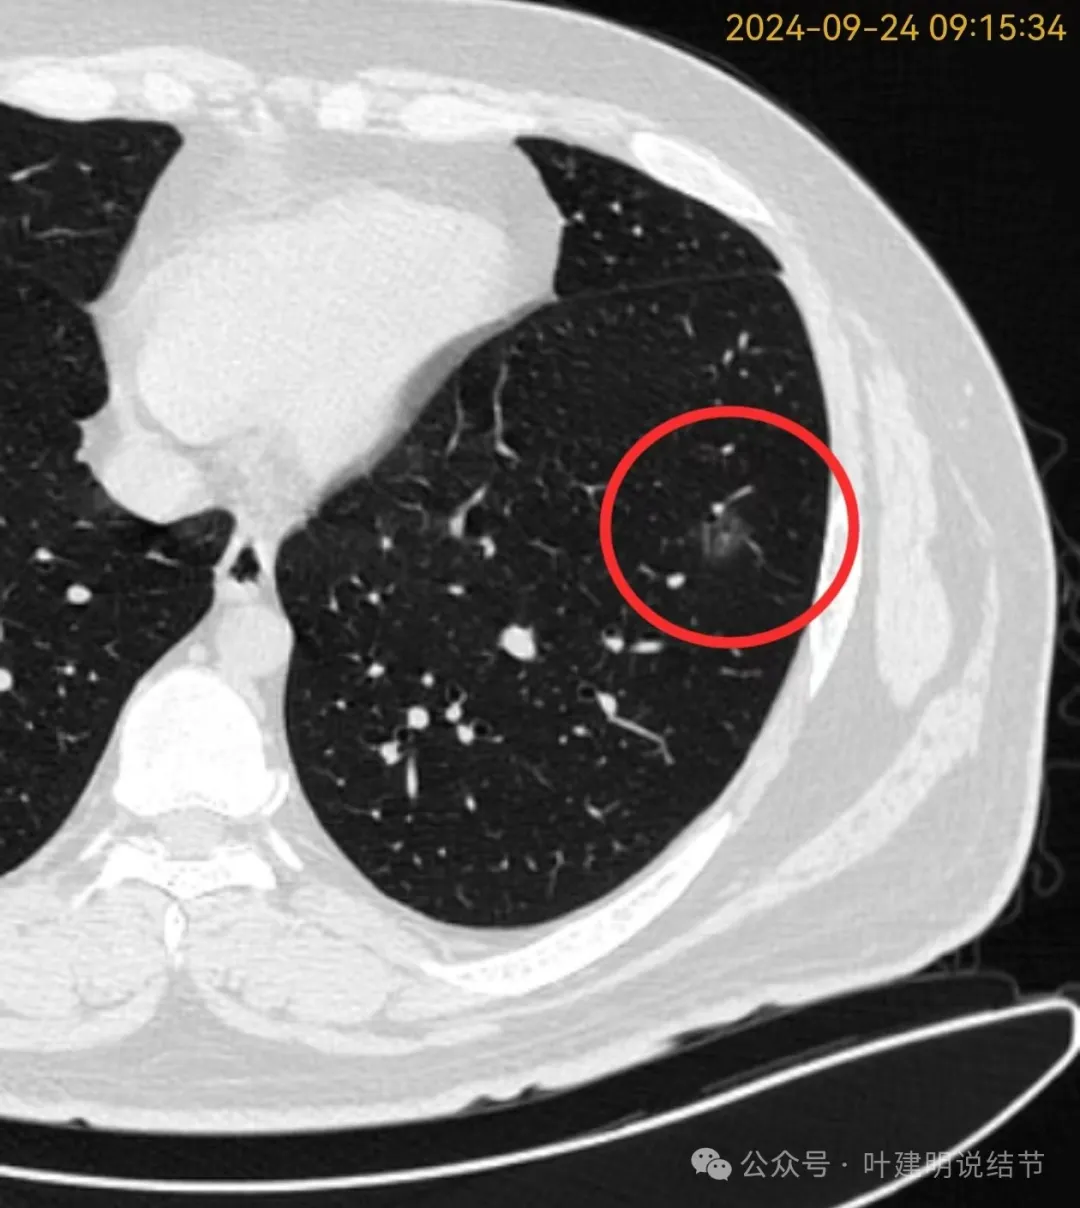

再看2024年9月复查的片子:

病灶出现,磨玻璃密度。有微小血管与细支气管通气征。

邻近细支气管扩张、边缘细毛刺、整体轮廓清。